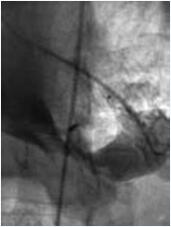

在超声透声图像欠佳或者发生与心尖部缺损封闭相关的其他并发症时,特别是成人患者、数个肌部缺损情况下,可以考虑“杂交”方法和介入方法结合进行(图10-51,图10-52)。笔者遇到一例成人肌部室间隔缺损患者,利用杂交手术的方法由于超声图像不清晰导丝无法通过缺损(胸骨正中小切口,心脏上部难以拖出、操作过程中TEE图像无法显示缺损)。

3个月后,介入医生成功关闭了患者的肌部缺损。其中的经验非常重要。应该结合这两种微创方法,为每一个个体选择最好的方法。这是笔者对微创的结合概念的理解。